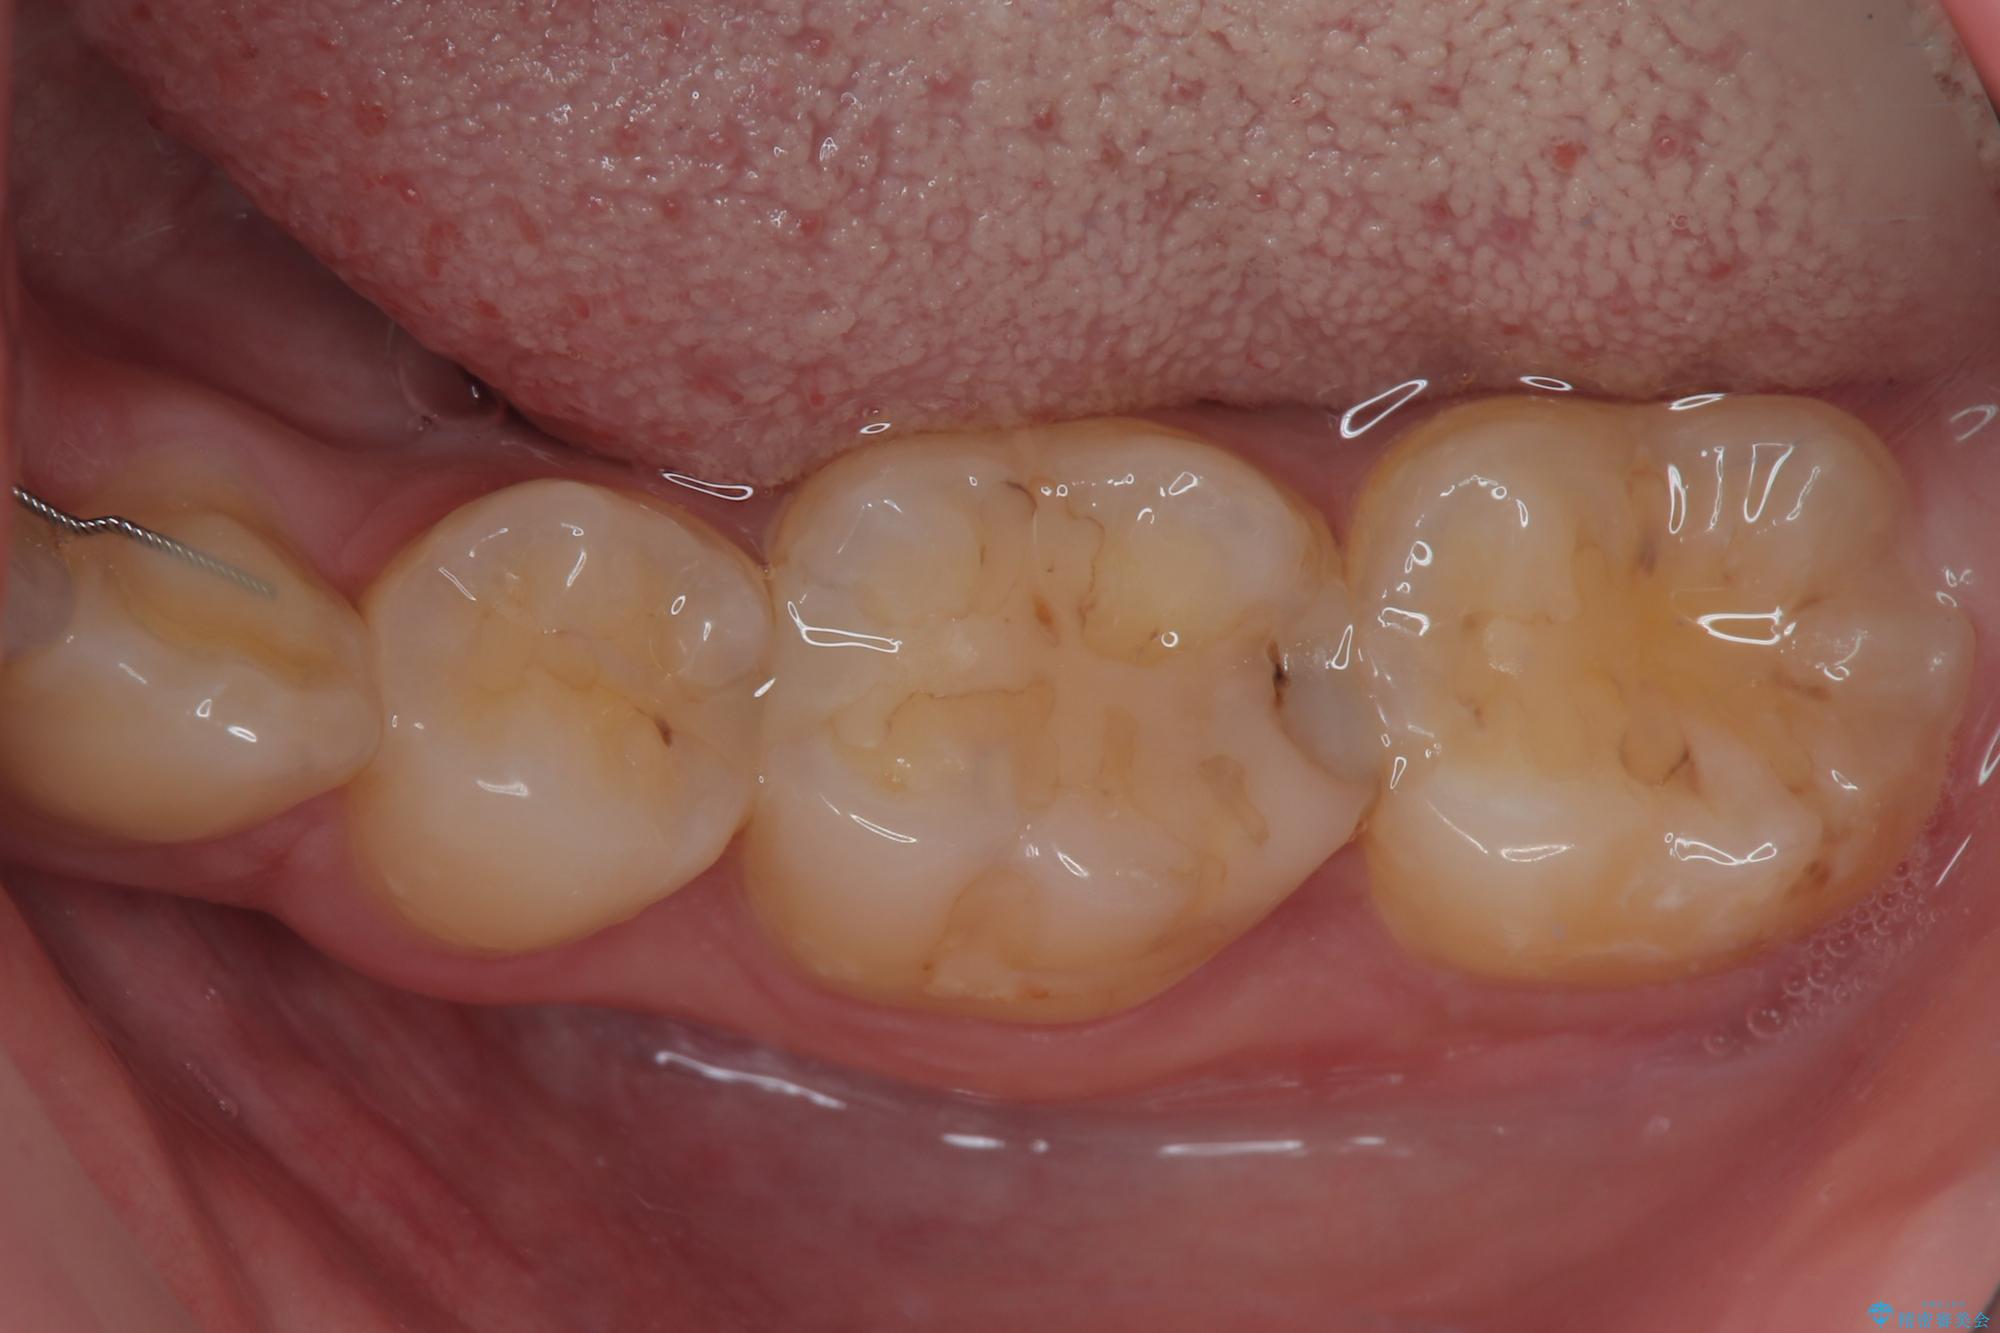

- 当院で矯正治療を終えて、左下が虫歯になっている気がするとのことで来院された患者様です。レントゲン検査の結果、コンポジットレジンによる修復箇所が複数行われており、詰め物の下に虫歯を認めました。

拡大鏡視野下でコンポジットレジン、虫歯の除去を行い、オールセラミッククラウンに適した形に整えました。